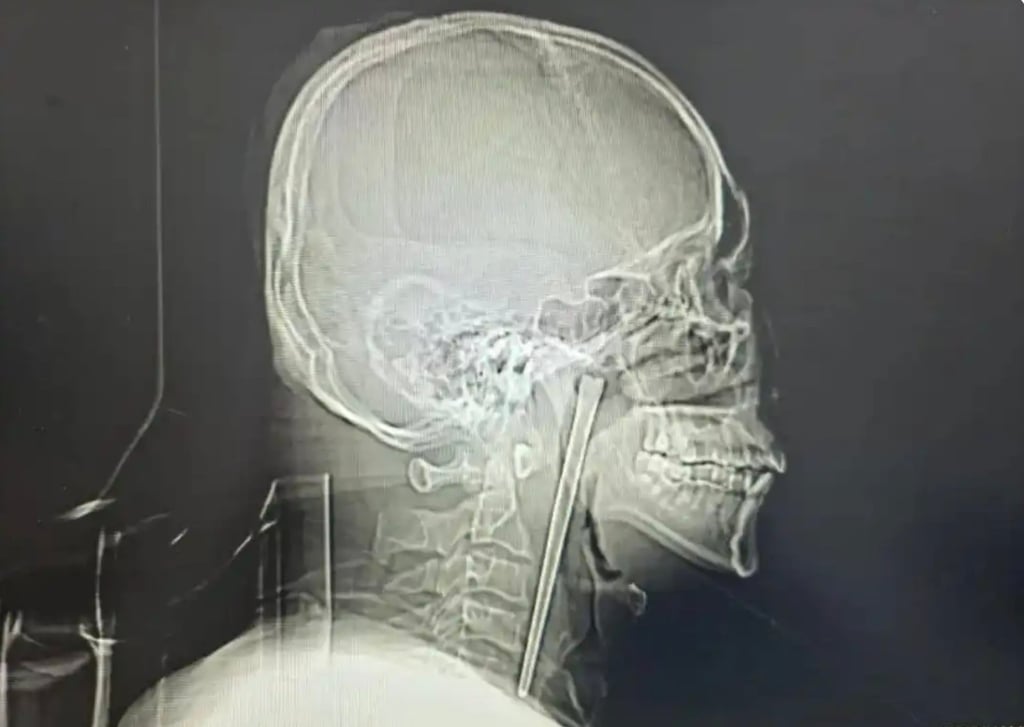

Một người đàn ông họ Vương tại Trung Quốc vừa trở thành tâm điểm chú ý trên mạng xã hội sau khi các bác sĩ phát hiện và lấy ra một chiếc đũa kim loại dài 12 cm đã nằm trong cổ họng ông suốt 8 năm. Câu chuyện không chỉ khiến nhiều người kinh ngạc mà còn đặt ra những câu hỏi về nhận thức sức khỏe và tâm lý sợ hãi phẫu thuật của bệnh nhân.

Các bác sĩ tại đây ban đầu không khỏi bất ngờ khi nghe bệnh nhân nói rằng chiếc đũa đã nằm trong cổ họng suốt 8 năm. Kết quả kiểm tra cho thấy dị vật nằm ở vùng vòm miệng mềm, một vị trí nhạy cảm nhưng may mắn là chưa gây tổn thương nghiêm trọng.

Theo đánh giá của đội ngũ y tế, niêm mạc xung quanh vẫn còn nguyên vẹn, các cơ quan liên quan không bị dịch chuyển và dây thanh âm vẫn hoạt động bình thường. Đây được xem là điều hiếm gặp, bởi một dị vật có kích thước lớn như vậy thường dễ gây ra biến chứng nguy hiểm nếu tồn tại lâu trong cơ thể.

Trước việc bệnh nhân tiếp tục từ chối phương án rạch cổ, các bác sĩ đã lựa chọn một giải pháp khác ít xâm lấn hơn, đó là tiến hành phẫu thuật qua đường miệng. Ca mổ được thực hiện cẩn thận và thành công khi chiếc đũa kim loại dài 12 cm được lấy ra mà chỉ gây chảy máu ở mức tối thiểu.